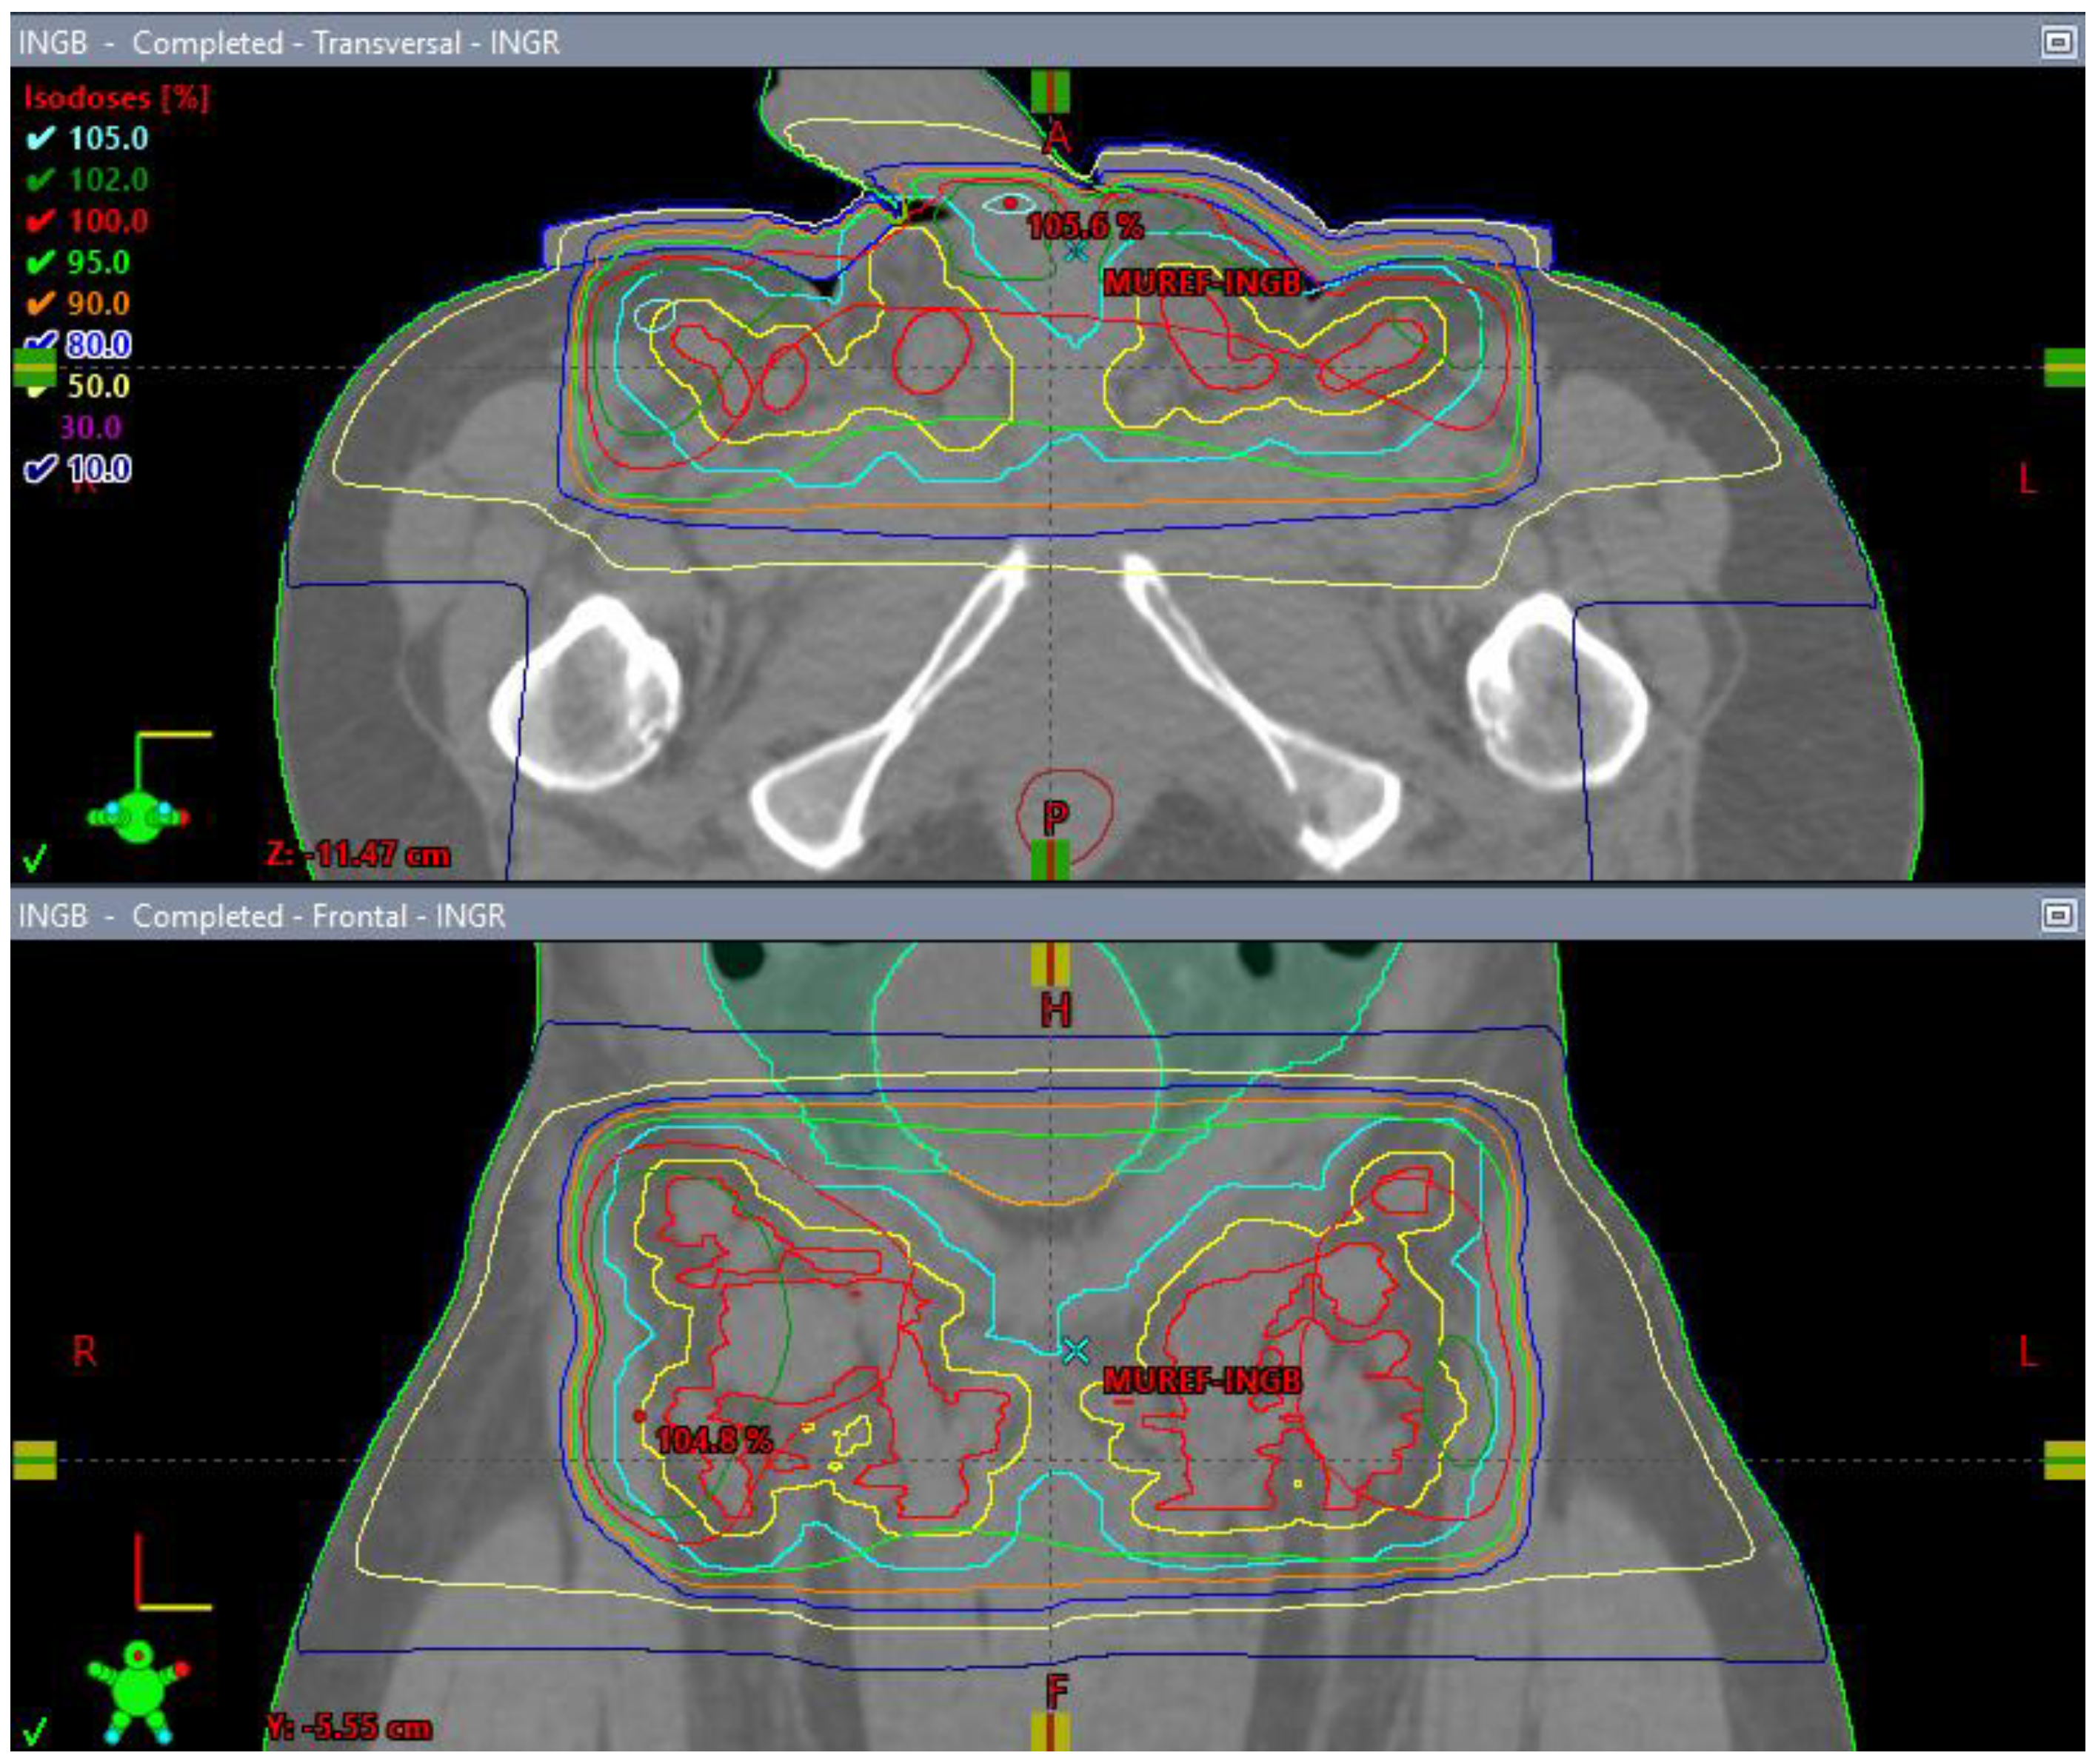

He began dose-reduced FOLFIRI chemotherapy with palliative intent, with the best response being progression after two cycles. His course was also complicated by rapid atrial flutter and hypotension requiring pressors, which were attributed to the progression of the thromboembolic disease, requiring an increase in the anticoagulation dose. Throughout these events, the patient’s principal complaint remained the persistent priapism and associated pain and psychological distress. He was connected to both the palliative care and psychiatry departments and continued follow-up with the urology department, who inserted a suprapubic catheter to reduce the urinary retention. The patient received palliative radiation (20 Gy in 5 fractions) to the groin with the goal of controlling his groin lymphadenopathy, which was thought to be contributing to his priapism (Figure 10A–D). There was a plan to initiate second-line FOLFOX shortly after completing the radiation treatment.

Figure 10.

3 Field (2 laterals (A,B) and 1 posterior (C) field) palliative radiation plan with 20 Gy/5 fractions to the inguinal nodes with a 1 cm bolus (D).